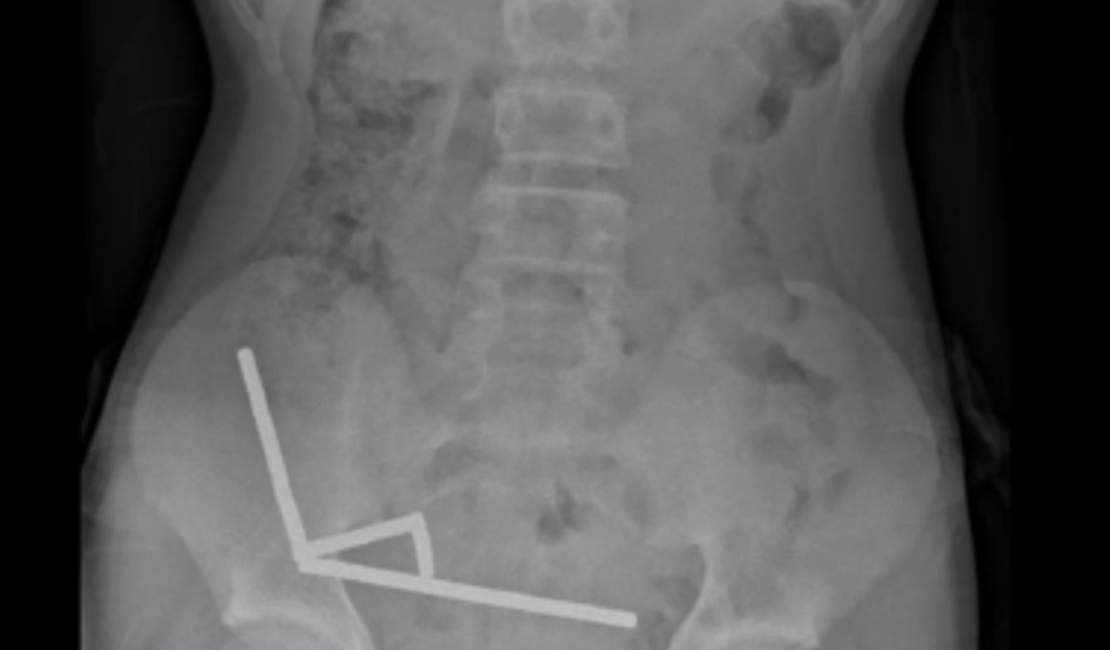

O garoto suportou quatro dias de intensa dor abdominal antes de procurar atendimento médico. No hospital, ele relatou ter engolido os ímãs cerca de uma semana antes. Exames mostraram que os objetos estavam agrupados em quatro correntes dentro do abdômen, conectando diferentes partes do intestino por meio da força magnética. Os médicos precisaram realizar uma cirurgia exploratória para remover os ímãs e tratar as áreas afetadas.

Durante o procedimento, os cirurgiões descobriram que os ímãs haviam causado necrose por pressão — morte do tecido intestinal provocada pela compressão prolongada. Parte do intestino delgado e do intestino grosso precisou ser retirada. Após oito dias de internação, o menino recebeu alta hospitalar.